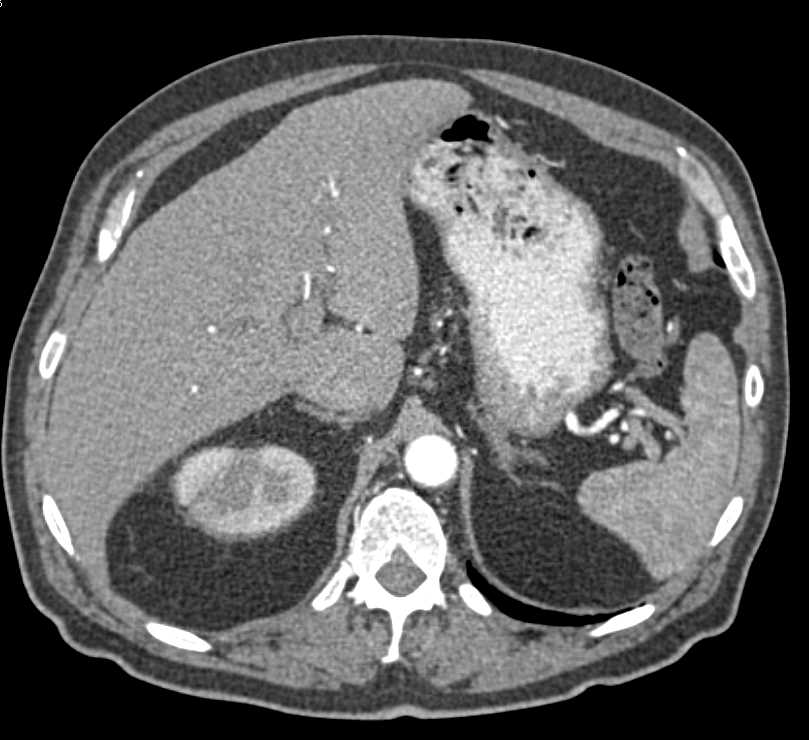

Acute Pyelonephritis Right Kidney